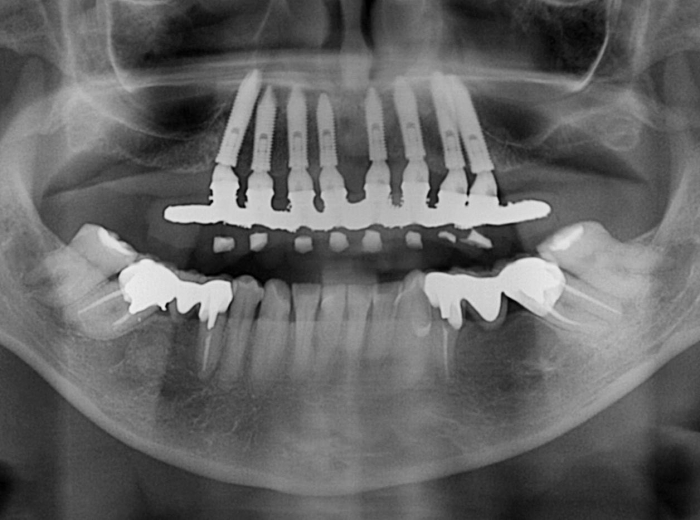

Raio X com a prótese fixa em resina, sobre implantes Cone Morse